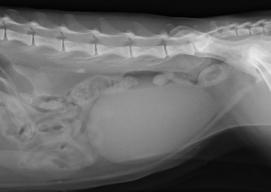

尿管結石による水腎症

体質、食事、尿路感染などにより結石が形成されます。腎臓、尿管、膀胱、尿道に存在し、尿管や尿道が詰まると重篤な症状を呈する場合があり注意が必要です。結石の存在している場所で治療が異なりますが、尿路閉塞がみられる場合は早急な処置、手術が必要となります。膀胱結石の場合は食事療法で結石が溶ける場合もあります。